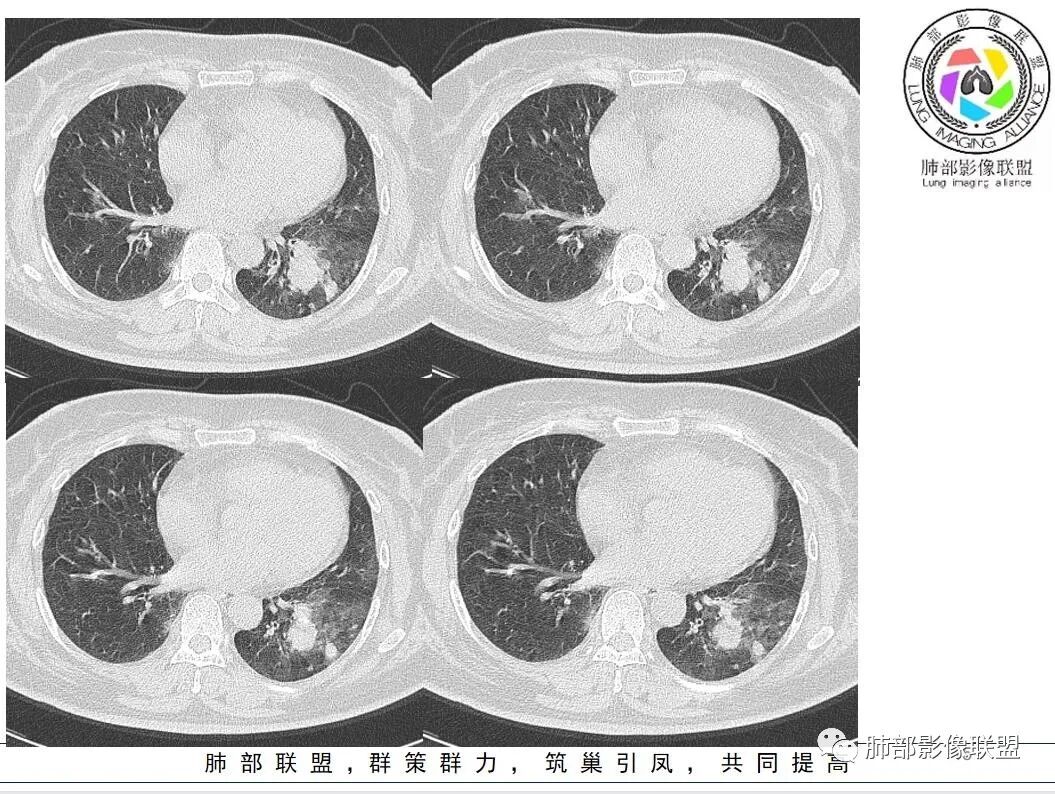

2. 影像表现:CT示左侧胸廓较对侧略塌陷,左肺下叶体积缩小,叶间裂略向左肺下叶轻度移位;双肺多发低密度空气潴留,以左肺下叶明显。左肺下叶团片状高密度影,可疑沿支气管血管束分布,病变近段支气管分支夹角增大,病变内见多支细支气管迂曲、牵拉扩张,部分细支气管达病变以远,病灶整体形态不规则,病变后内侧局部膨隆较明显,邻近叶间裂牵拉凹陷,图像伪影明显,病灶边缘可疑伴有磨玻璃晕等,邻近背侧胸膜多处增厚且范围较广;病变以远肺组织见局限性肺野透亮度增加,病变周围见多发实性结节;增强扫描病灶呈相对均匀强化。另左肺下叶部分支气管管壁增厚,局部肺野密度增高。病变部分边界清楚,局部可见月牙铲及胸膜凹陷征,胸膜牵拉僵直。

3.病例小结:本例外伤后意外发现,缺乏发热及呼吸系统相关临床表现,也没有提供相关的血常规、血沉、CRP、hs-CRP、降钙素原等炎性指标情况,不宜首先考虑普通感染性病变,但是此患者有糖尿病基础,灶周多发结节,因此结核等特殊感染需要排除,尽管缺乏典型树芽征。CT病灶抱团,膨隆感较明显,缺乏平直征、刀切征等,病灶周围可疑磨玻璃晕,增强相对均匀强化,该患者为老年无相关症状患者,恶性肿瘤要警惕,又是女性患者,加上胸膜凹陷征、扩张的充气支气管征等等,腺癌等恶性病灶应当重点鉴别,可惜缺乏既往影像资料对比。